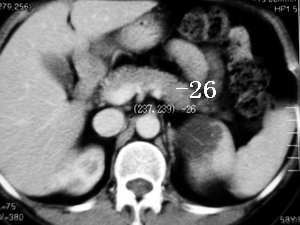

应该为脾脏来源的,囊性肿瘤,从前后ct片显示,有轻度强化改变(ct值),但好像有快速消退的感觉???

ct示脾内缘囊性低密度影,强化后其边缘实质部分与脾同步,且强化程度一样,

脾脏来源的,低密度,边界清,有分隔,有强化。

左侧肾上腺受压,病变不是来源于肾上腺,mri脂肪抑制病变为高信号,除外脂肪瘤,考虑来源于脾脏可能性大,强化后壁与脾脏强化基本相似,其内见分隔,囊腺瘤,血管瘤不除外。

首先病灶的部位位于脾脏,这一点应该可以达成共识,因为它相邻的实质部分与脾脏同期.同时强化,并可见“鸟嘴”征象。第2:囊性病灶没有明显强化,在延期扫描的时候也是一样。也无病灶缩小的特征。所以我感觉应该考虑:脾脏囊性占位(脾脏囊肿可能性大)

同意大多数同仁意见,关键在于+c上明显显示脾动脉一分支走向囊肿边缘,同时与肾上腺无关.